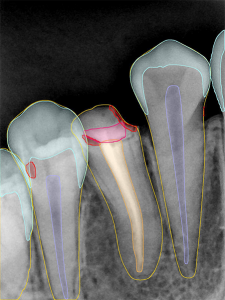

- Restoration Analysis

Identify restorative materials for treatment evaluation